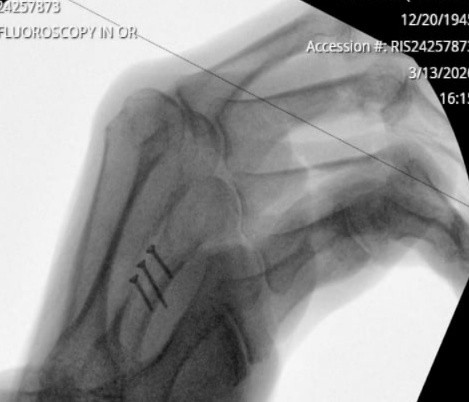

Anyone squeamish about seeing anatomical parts exposed on film should turn away for a moment.

I have been advised that the attached graphic is not “too” graphic to be shared here. This is the inside view of the finger repair showing the angle of the breakage and the three surgical screws needed to attach the two halves of the finger. As you can see, no one can now say that “I have a screw loose”

I have empathy for anyone in the medical or health care profession, exposed to me. I do tend to Wramble when I am in receipt of their services. The most recent was, and who fully earned my utmost respect for yet another of the JMH employees. Jason Szabo, who removed the stitches from my repaired ring finger had been in attendance when Dr. Mansour did the surgery on my ring finger and was able to explain thoroughly how the entire process unfolded and why they had to use three screws to hold the broken halves together.

The screws will be implanted in my finger and my mind, and now with me forever. The fracture was a diagonal displacement of the metacarpal bone and would not stay aligned since the break line was longitudinal to the finger. “long…” is the key component of that last term.